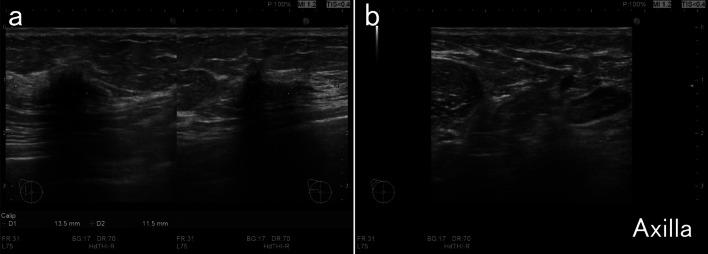

A 73-year-old woman with a history of ovarian cancer and diabetes presented with right focal asymmetric density on a mammogram acquired during routine breast cancer screening. Ultrasonography (US) and magnetic resonance imaging (MRI) showed a 13.5-mm tumor in the upper lateral region of the right breast. A US-guided Mammotome biopsy revealed invasive ductal carcinoma of the right breast. Preoperative assessments including positron emission tomography-computerized tomography, found no evidence of axillary lymphadenopathy or distant metastasis. Because the breast cancer was stage I, the patient underwent a right mastectomy and a sentinel lymph node biopsy (SLNB) at our hospital. Pathological assessment of the biopsy revealed follicular lymphoma (FL), but no metastatic breast cancer. The patient was referred to hematology to stage the FL. Bone marrow findings were negative and stage I FL was diagnosed. After the mastectomy, she was monitored and given adjuvant therapy with an aromatase inhibitor.